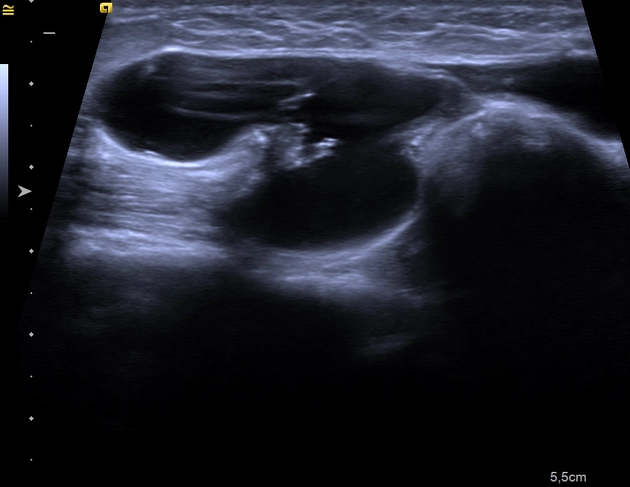

Thoát vị ống Nuck (Canal of Nuck hernia)

Nang nước ống Nuck (Hydrocele of the canal of Nuck)